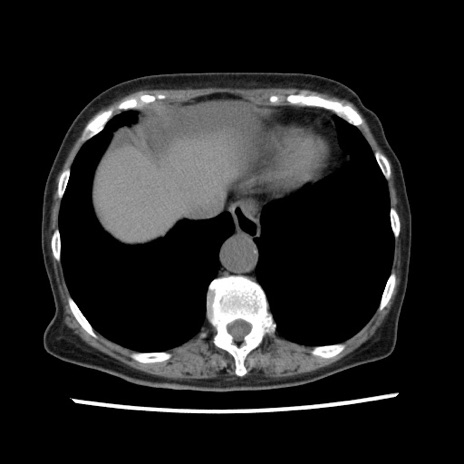

症例1(横断像)

【症例】80歳代女性

【主訴】腹痛

【現病歴】8時間前から腹痛あり来院。

【既往歴】糖尿病、脂質異常症、子宮体癌にて子宮全摘術

【身体所見】意識清明・会話良好だが腹痛で苦悶様、全腹部にわたって反跳痛と圧痛あり

【データ】WBC 13600、CRP 0.14、LDH 224、CK 90